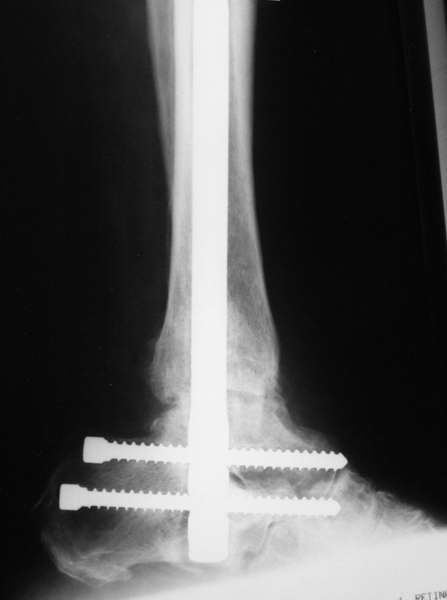

Можно: 65-летняя пациентка, оперирована по поводу несросшегося в гипсе перелома лодыжек с патологической вальгусной установкой стопы и выраженным нарушением опрной функции. Оперирована через 6 месяцев после травмы. Рентгенограммы через 4 месяца после операции.

Уважаемый А.Семенистый. Складывается впечатление, что вы выполнили трехсуставный артродез, уж больно длинные блокирующие винты. Не мешают ли они пациентке при ходьбе?